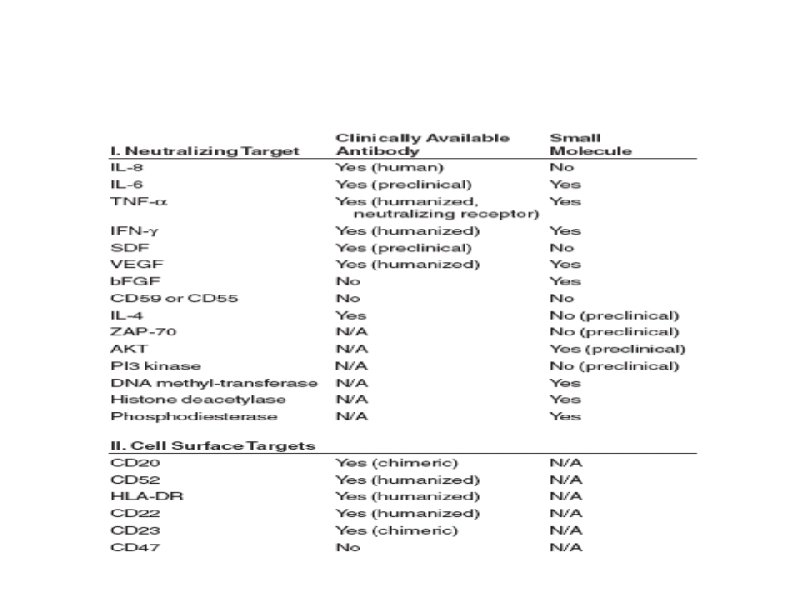

Время удвоения лимфоцитов менее 6 месяцев Время удвоения лимфоцитов более 6 месяцев Стадия на момент диагноза III – IV / C (Rai / Binnet) Возраст менее 65 лет I – II / A Возраст более 65 лет ZAP-70 < 20% Соматическая мутация (-) Соматическая мутация (+) 17 p делеция (p 53 мутация), 13 q делеция 11 q делеция, 12 q трисомия CD 38 (+) CD 38 (-)

Факторы, влияющие на выбор терапии больных ХЛЛ

Тактика лечения больных ХЛЛ на постремиссионном этапе